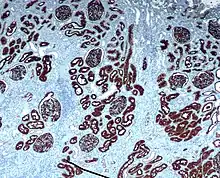

Immunohistochemical staining is widely used in the diagnosis of abnormal cells such as those found in cancerous tumors. In some cancer cells certain tumor antigens are expressed which make it possible to detect. Immunohistochemistry is also widely used in basic research, to understand the distribution and localization of biomarkers and differentially expressed proteins in different parts of a biological tissue.[3]

Reporter molecules vary based on the nature of the detection method, the most common being chromogenic and fluorescence detection. In chromogenic immunohistochemistry an antibody is conjugated to an enzyme, such as alkaline phosphate (AP) and horseradish peroxidase (HRP), that can catalyze a color-producing reaction in the presence of a chromogenic substrate like diaminobenzidine (DAB).[4] The colored product can be analyzed with an ordinary light microscope.[10] In immunofluorescence the antibody is tagged to a fluorophore, such as fluorescein isothiocyanate (FITC), tetramethylrhodamine isothiocyanate (TRITC), aminomethyl Coumarin acetate (AMCA) or Cyanine5 (Cy5). Synthetic fluorochromes from Alexa Fluors is also commonly used.[10][11] The fluorochromes can be visualized by a fluorescence or confocal microscope.[10]

After immunohistochemical staining of the target antigen, another stain is often applied. The counterstain provide contrast that helps the primary stain stand out and makes it easier to examine the tissue morphology. It also helps with orientation and visualization of the tissue section. Hematoxylin is commonly used.[5][12]